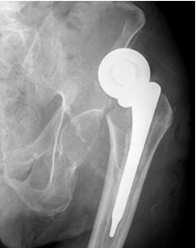

Fig 120. Luxación de prótesis.

A: Rx AP. Luxación superior de prótesis unipolar.